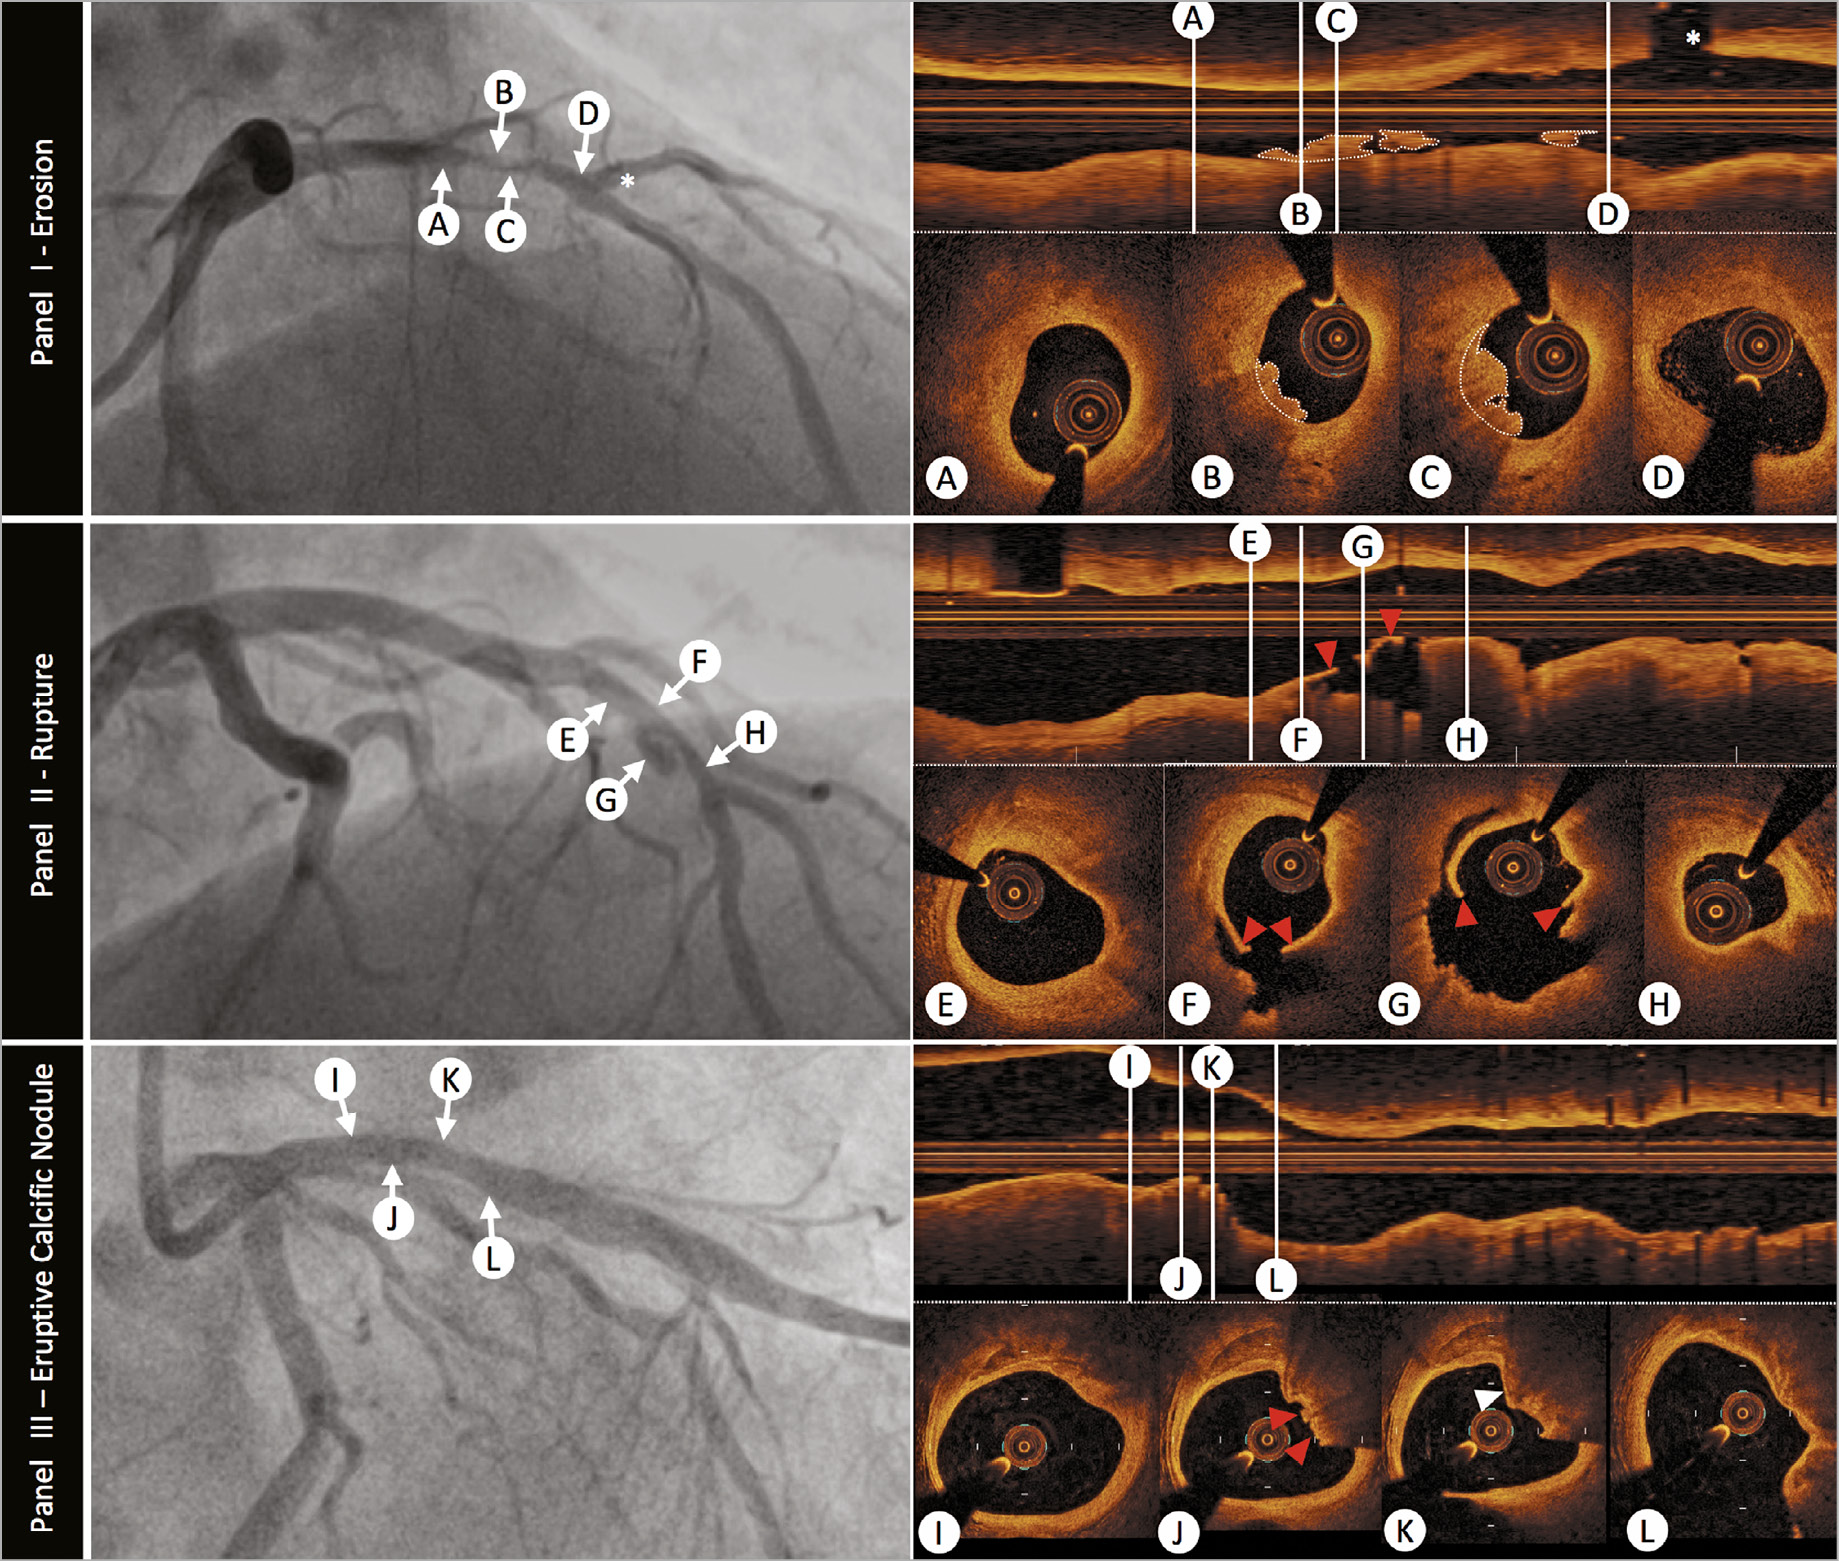

Plaque rupture is defined by discontinuity of the fibrous cap overlying a lipid-rich core (Figure 3). Ruptured fibrous cap-ACS is commonly associated with a vessel wall cavity, without IVUS or OCT signal, generated through downstream embolization of the necrotic core. Thrombi are often found overlying the ruptured segment. However, thrombus may be absent at the site of an old plaque rupture or with fresh rupture treated with anti-thrombotic/anti-coagulant therapies. Multiple plaque rupture sitesmay be evident and differences between culprit and non-culprit lesions have been observed, with the presence of thrombus, smaller luminal area, and greater plaque burden associated with culprit lesions.19

Figure 3. The role of optical coherence tomography to define atherosclerotic acute coronary syndrome plaque aetiology. Panel I: plaque erosion –angiographic image shows a severe stenosis in the mid-left anterior descending coronary artery (indicated by arrows B and C). Serial intravascular optical coherence tomography cross-sectional images indicate that no rupture is detected in the culprit lesion. Optical coherence tomography-erosion is identified as an irregular lumen surface with attached mural thrombus (white dotted outline on cross-sections and longitudinal image) overlying a fibrous plaque (B and C). Cross-sectional images indicate thick-cap fibro-atheroma proximal (A) and distal (D) to thrombus, immediately before a major diagonal branch (white asterisk). Panel II: plaque rupture –angiogram demonstrates a culprit lesion in the left anterior descending coronary artery (indicated by arrows F and G). Plaque rupture is identified on cross-sectional and longitudinal optical coherence tomography images by the disrupted fibrous-cap (red arrowheads) and a cavity formation inside the plaque (F and G). Cross-sectional images indicate optical coherence tomography-defined thin-cap fibroatheroma in the proximal (E) and distal (H) segments of the culprit lesion. Panel III: eruptive calcific nodule –angiography demonstrates a moderate lesion in the proximal left anterior descending artery (indicated by arrows J and K). Optical coherence tomography evaluation of the vessel confirms calcific infiltration of the vessel wall. The distinct margins of a superficial calcific sheet are demonstrated in Panel III-I from 11 o’clock to 2 o’clock. Disruption of the luminal contour with overlying red thrombus (red arrowheads), resulting in image attenuation (12-3 o’clock) is evident in Panel III-J. Immediately downstream the irregular protrusion of the calcific nodule is better delineated (Panel III-K white arrowhead). It is important to note that the nodule generates significant attenuation, obscuring deeper vessel structures, and this can result in misclassification as red thrombus. Endothelial integrity is confirmed more distally (Panel III-L).

Plaque erosion is characterized by endothelial denudation, a poorly understood pathological process occurring at a level that is undetectable by current intracoronary imaging modalities. Only OCT has been successfully used, in clinical practice, to identify plaque erosion, although the diagnosis is one of exclusion, where thrombus is associated with non-disrupted plaque. An OCT diagnosis of plaque erosion is considered ‘definite’ in the absence of fibrous cap disruption, in a lesion frequently composed of fibrous tissue, with overlying luminal white thrombus. A ‘probable’ OCT-erosion may lack luminal thrombus but demonstrates an irregular luminal surface, or has overlying thrombus with attenuation of the underlying plaque, without evidence of superficial lipid or calcification in the vessel upstream or downstream of the thrombus site16 (Figure 3). Effective blood clearance is very important to minimize the potential for misdiagnosing OCT-erosion secondary to streaming of blood, particularly when in contact with the lumen wall.

ERUPTIVE CALCIFIC NODULE

Discrete calcific nodule with associated plaque disruption is the least frequently observed substrate for ACS but can pose significant challenges for stent deployment and optimization. The process was first identified by IVUS24 with subsequent pathological studies demonstrating that eruptive calcific nodules are responsible for 2-7% of acute coronary events.25 The lesions exhibit breaks in a calcified plate that disrupt the fibrous cap and are overlaid by thrombus.26 Imaging of erupted calcific nodule is possible with IVUS and OCT, with OCT providing superior detection of thrombus, delineation of superficial and deep boundaries of calcium and plaque disruption (Figure 3). However, there are limitations to OCT imaging, for example, the presence of protruding calcium can pose challenges in tissue differentiation, particularly through attenuation of deeper structures resulting in mis-representation as red thrombus and potential misdiagnosis of an acute culprit event. Similarly, distinguishing lipid core from calcium, if the boundaries are ill-defined, or detecting calcium when there is overlying thrombus can be better achieved with IVUS and virtual histology (VH)-IVUS.27

Histopathological comparison has demonstrated that OCT can differentiate various types of coronary calcification and accurately detect calcific nodules. In clinical OCT studies, an eruptive calcific nodule has been defined as a lesion that exhibits evidence of fibrous cap discontinuity and/or thrombus, over a calcified plaque characterized by protruding calcification into the lumen, and the presence of substantive calcium proximal and/or distal to the lesion.16 Intervention in ACS patients presenting with eruptive calcific nodules is associated with higher target lesion revascularization rates, highlighting the complex nature, and challenging treatment of this lesion subset.28 Recently, analysis of a large core laboratory OCT series has proposed additional calcific lesion substrate for ACS, specifically superficial calcific sheets, which were associated with greater post-PCI myocardial injury.29